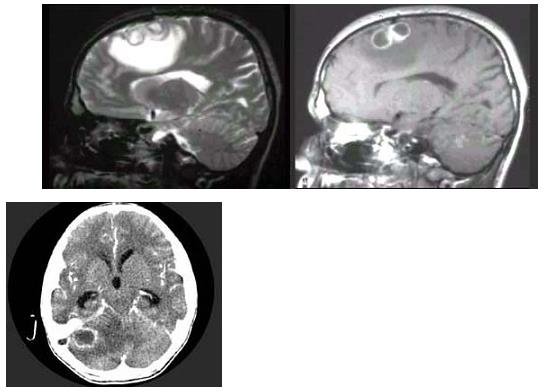

4、 男,36岁,1周前出现全身发热、头痛、乏力,经过对症治疗病情好转,随后再次出现头痛,伴有恶心、呕吐,急到医院检查,MRI检查如图,最可韶的诊断为()。

- A、星形细胞瘤

- B、转移瘤

- C、脑脓肿

- D、脑梗死

- E、脑内血肿

【正确答案-参考解析】:参加考试可见 点击进入查看